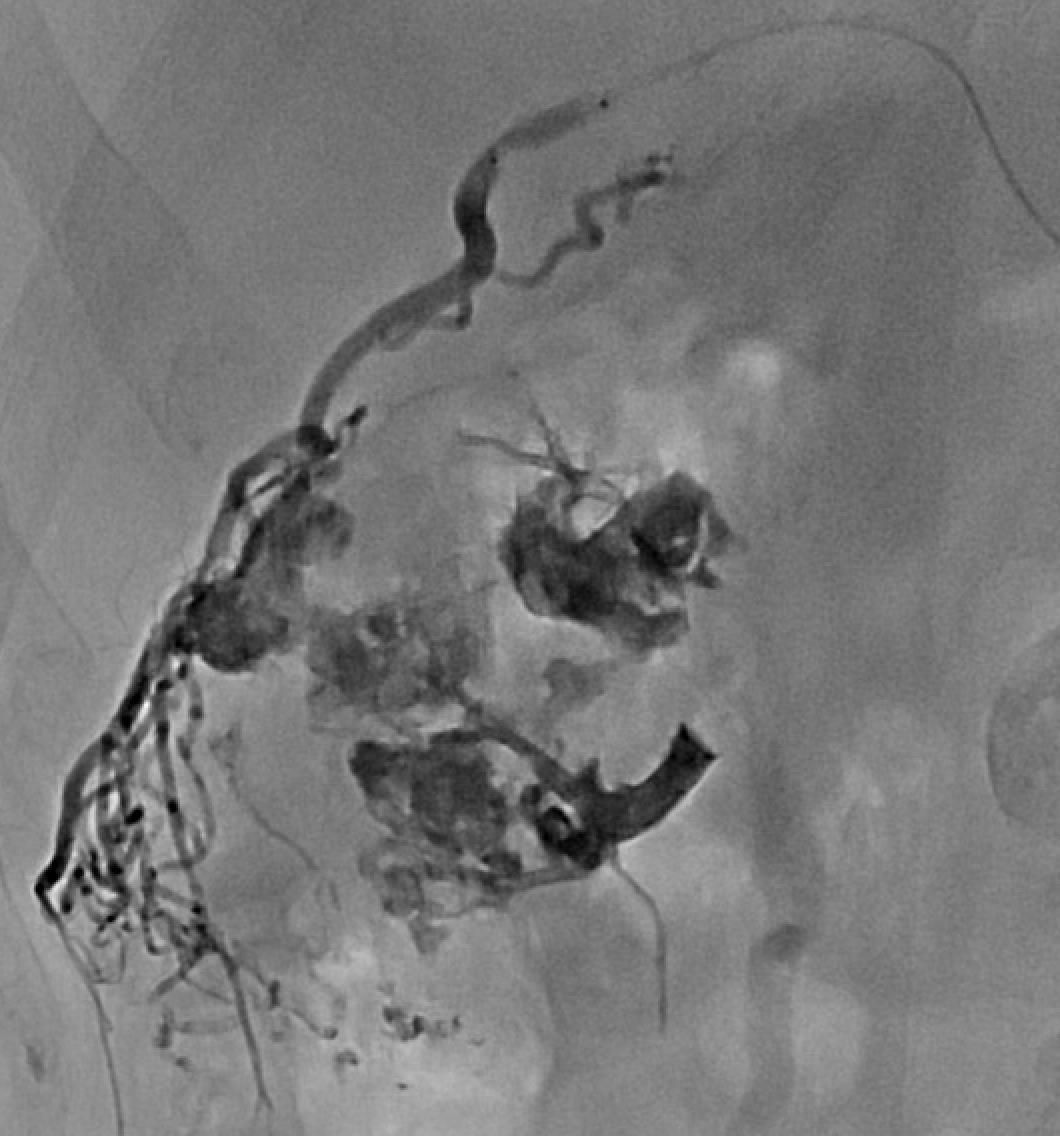

Dossier 1 : Volumineuse malformation artérioveineuse rénale, vraisemblablement secondaire à un carcinome à cellules claires du rein droit, de présentation atypique. Embolisation artérielle au 𝗦𝗾𝘂𝗶𝗱 (Balt) et au 𝗚𝗹𝘂𝗯𝗿𝗮𝗻 𝟮, à l’aide d’un micro-cathéter à ballonnet afin de ralentir le flux.